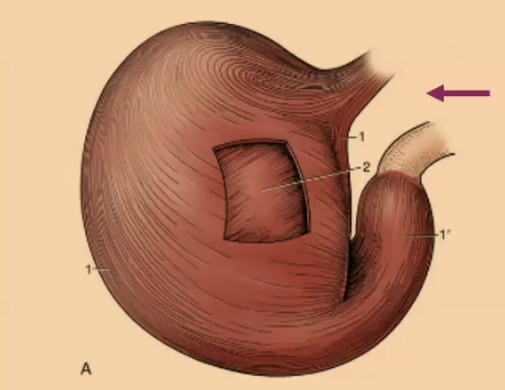

T/F: The simple stomach is fully within the ribcage.

True

#1

Cardia

#2

Fundus

#3

Body

#4

Pyloric

Is the pyloric portion of the simple stomach found more on the right or left?

right

Is the cardia of the simple stomach found more on the right or left?

left

What are folds of the stomach called and their purpose?

Rugae, surface area for secretion/digestion

What is shown by the purple arrow?

Rectum